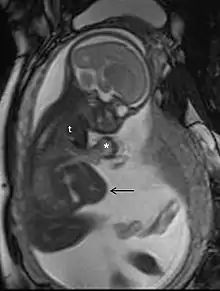

Magnetic resonance imaging (MRI), without MRI contrast agents, is not associated with any risk for the mother or the fetus, and together with medical ultrasonography, it is the technique of choice for medical imaging in pregnancy.[1]

MRI is commonly used in pregnant women with acute abdominal pain and/or pelvic pain, or in suspected neurological disorders, placental diseases, tumors, infections, and/or cardiovascular diseases.[3] Appropriate use criteria by the American College of Radiology give a rating of ≥7 (usually appropriate) for non-contrast MRI for the following conditions: